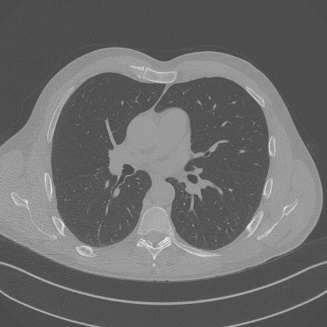

Low-Dose Computed Tomography (LDCT) technique, which reduces the radiation harm to human bodies, is now attracting increasing interest in the medical imaging field. As the image quality is degraded by low dose radiation, LDCT exams require specialized reconstruction methods or denoising algorithms. However, most of the recent effective methods overlook the inner-structure of the original projection data (sinogram) which limits their denoising ability. The inner-structure of the sinogram represents special characteristics of the data in the sinogram domain. By maintaining this structure while denoising, the noise can be obviously restrained. Therefore, we propose an LDCT denoising network namely Sinogram Inner-Structure Transformer (SIST) to reduce the noise by utilizing the inner-structure in the sinogram domain. Specifically, we study the CT imaging mechanism and statistical characteristics of sinogram to design the sinogram inner-structure loss including the global and local inner-structure for restoring high-quality CT images. Besides, we propose a sinogram transformer module to better extract sinogram features. The transformer architecture using a self-attention mechanism can exploit interrelations between projections of different view angles, which achieves an outstanding performance in sinogram denoising. Furthermore, in order to improve the performance in the image domain, we propose the image reconstruction module to complementarily denoise both in the sinogram and image domain.